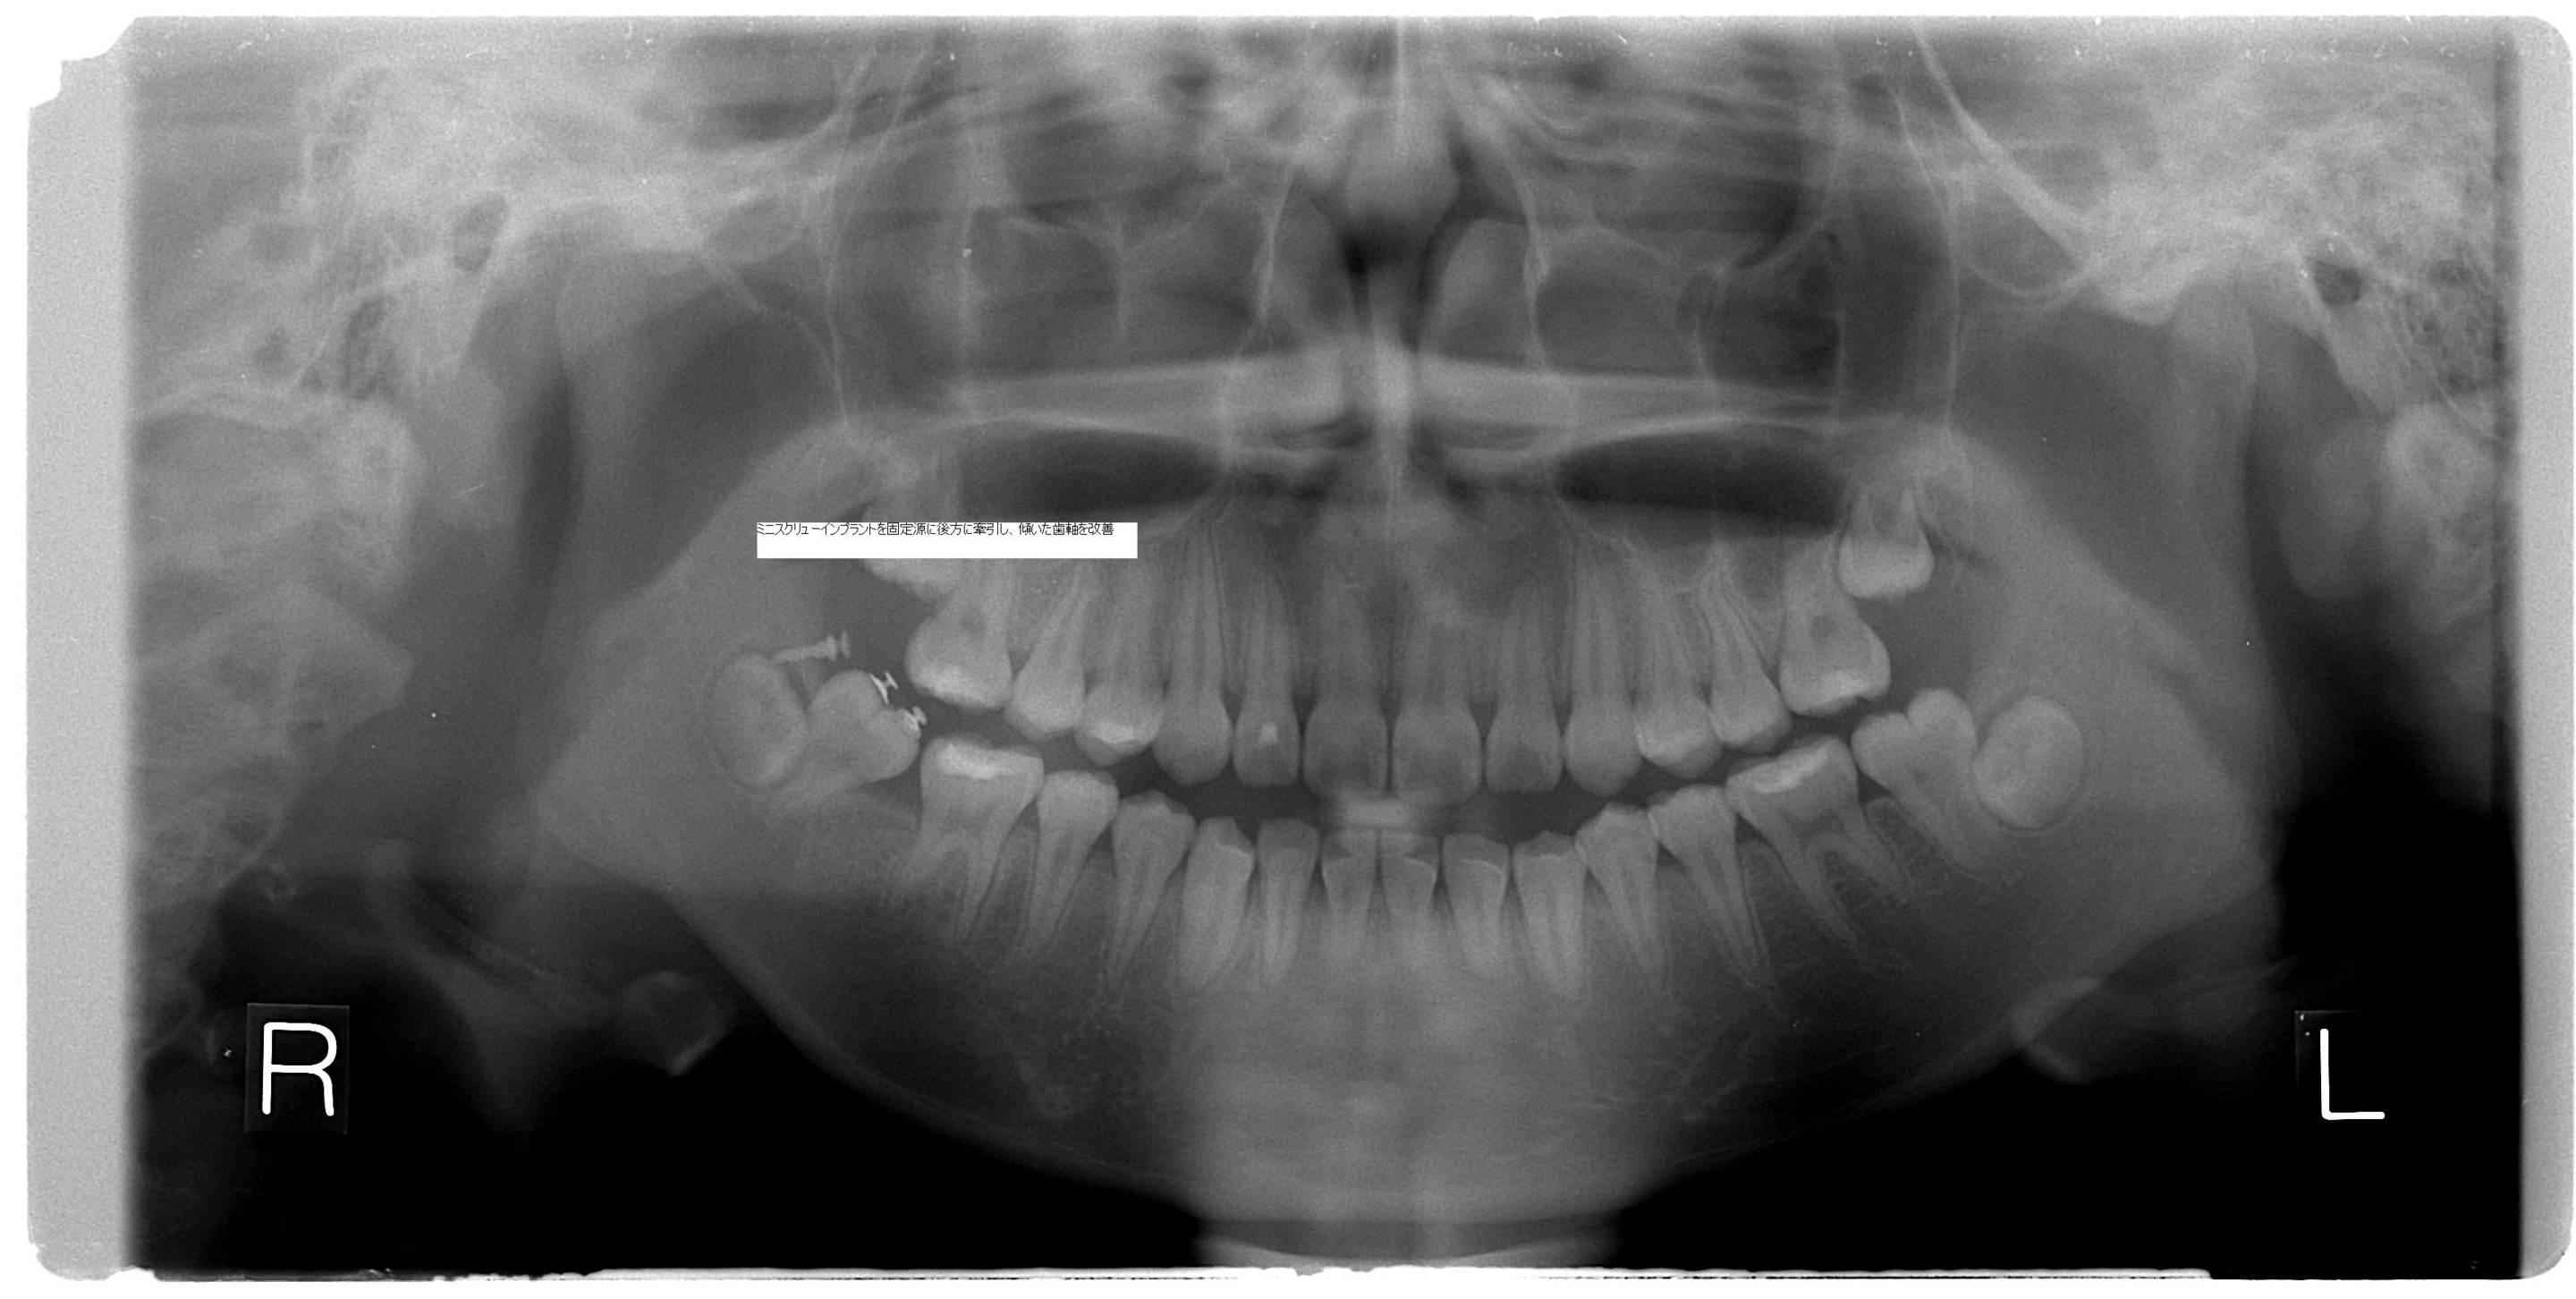

インプラント(ミニスクリュー)矯正について

インプラント矯正とは

歯科矯正用の小さなスクリュー(ねじ)を歯茎の骨に埋入して、歯を動かすときの固定源として用いる方法です。ねじ自体は直径1.4~2mm前後、長さは6~10mmです。

レントゲンなどの資料から、固定源となるねじの埋入部位や埋入方向の検討を行います。